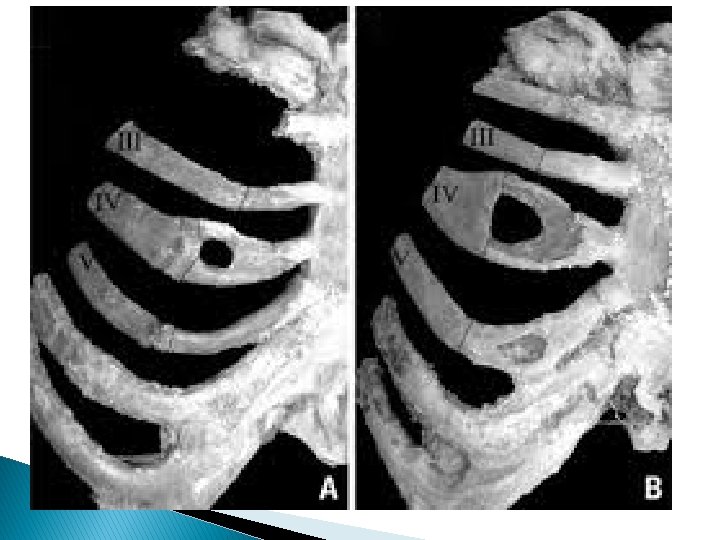

Rib Fractures � Fifth to Ninth ribs : can be single or multiple. Multiple fractures can present as flail chest, which is present when paradoxical respiratory movement occurs in a segment of the chest wall. This type of fracture requires at least 2 segmental fractures in each of 3 adjacent ribs, the costal cartilages, or the sternum

Flail chest � Flail chest is traditionally described as the paradoxical movement of a segment of chest wall caused by fractures of 3 or more ribs anteriorly and posteriorly within each rib. � Variations include posterior flail segments, and flail including the sternum with ribs on both sides of the thoracic cage fractured. � Severe blunt trauma